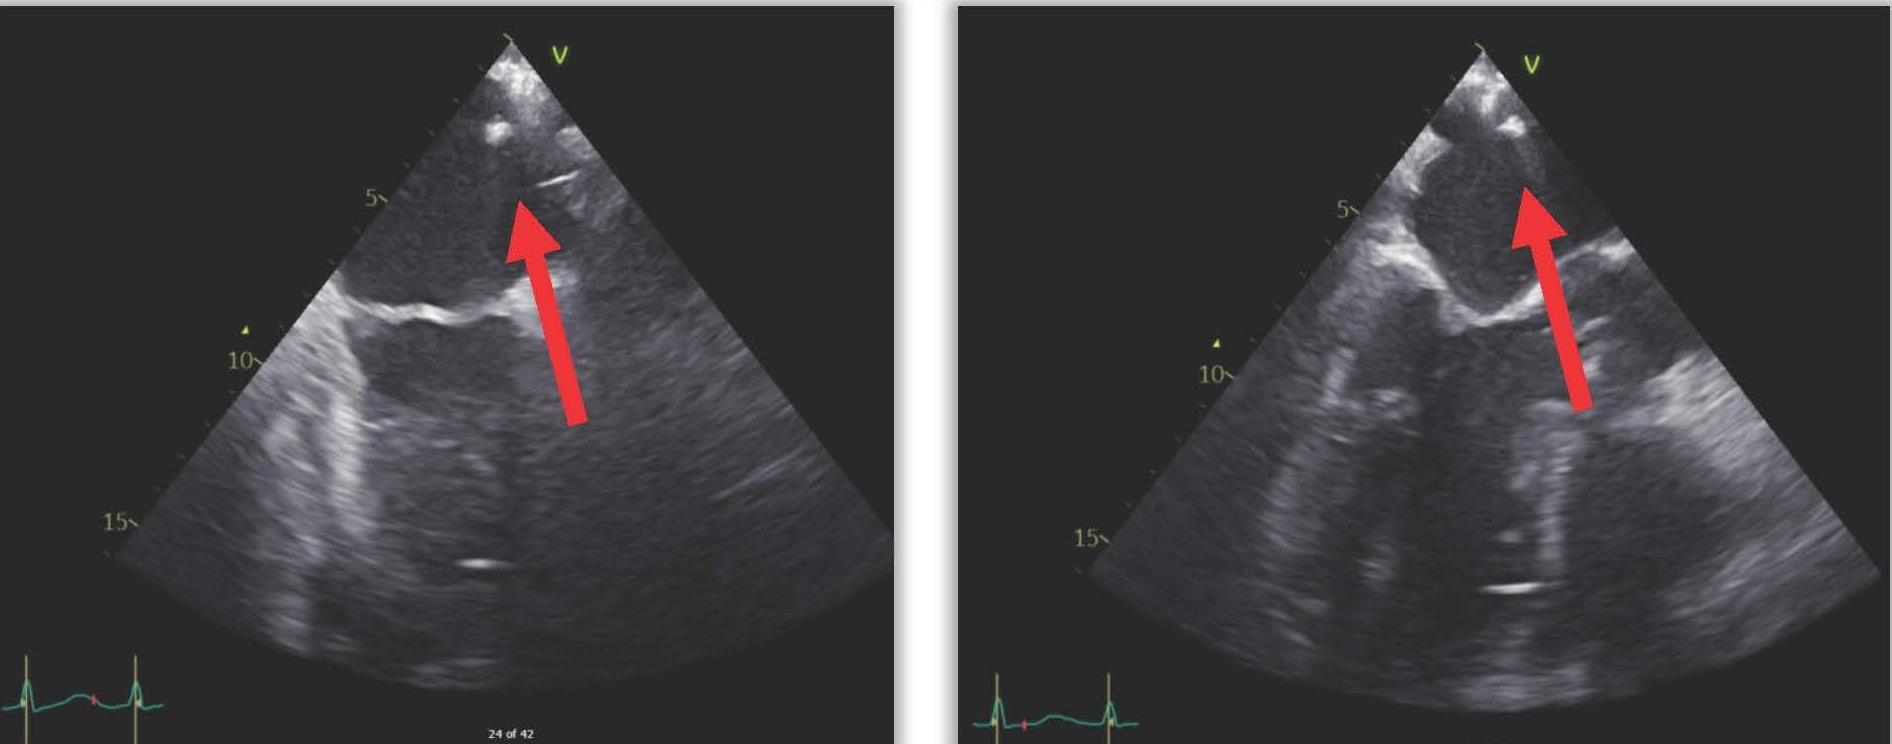

The next day (25 days post-ablation), the patient experienced significant neurological deterioration, with a GCS score dropping to 3/15, supraventricular tachycardia at 122 beats per minute, severe hypotension, and tachypnea with a respiratory rate of 36 per minute. A purpuric rash appeared on the neck, chest, and shoulders, and the patient was febrile with a temperature of 40°C. Due to the severe neurological and septic presentation, he was admitted to the ICU, intubated, and placed on mechanical ventilation. Invasive monitoring and hemodynamic support were initiated. Blood tests showed a marked increase in C-reactive protein (210 mg/L), a white blood cell count of 7.16 x 10^3/µL (65% neutrophils), and significant renal function deterioration. First blood cultures identified multisensitive Streptococcus salivarius, leading to the initiation of antibiotic therapy with amikacin and ceftriaxone for suspected endocarditis. The lumbar puncture was sterile. Transesophageal echocardiography (TEE) later revealed a highly echogenic mass attached to the left pulmonary vein's ostium (Figure 1), severe left ventricular dysfunction, and air bubbles in cardiac cavities (Figure 2). A contrast-enhanced thoracic CT scan showed air in the left atrium and findings consistent with mediastinitis (Figure 3).

Figure 1. TEE showing an echogenic mass moving in the left atrium.

Figure 2. TEE showing air bubbles in intracardiac cavities.